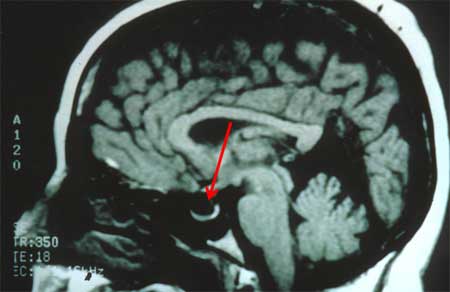

Idiopathic intracranial hypertension

MRI of empty sella on sagittal view

From the personal collection of Dr M. Wall; used with permission